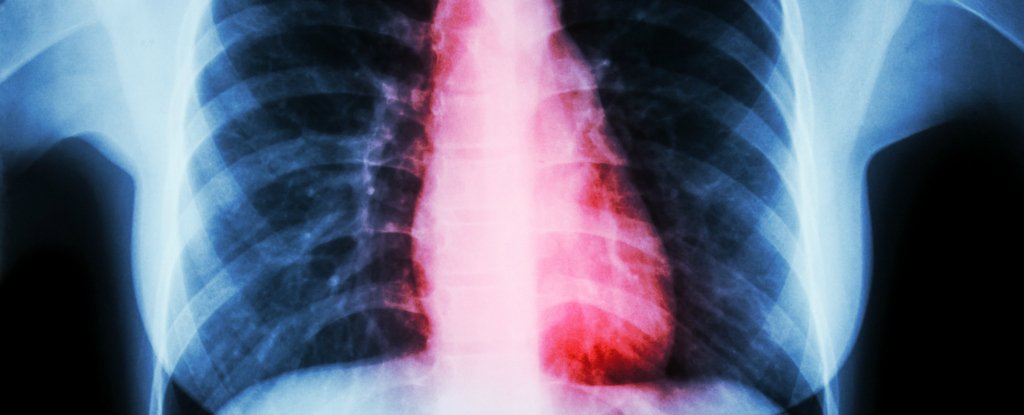

Mas quando Simpson chegou às instalações médicas, os profissionais realizaram vários testes e diagnosticaram algo totalmente diferente de um ataque cardíaco. Eles descobriram que Simpson estava sofrendo de “cardiomiopatia Takotsubo”, também conhecida como “cardiomiopatia por estresse”, que é uma condição que imita os sintomas de um ataque cardíaco regular.

A cardiomiopatia de Takotsubo normalmente de eventos ruins, causadores de altos níveis de estresse e ansiedade. No caso de Simpson, ela sofria da dor de um coração quebrado, após a perda de seu companheirinho, Meha.

Por causa disso, a doença também é chamada de ”síndrome do coração partido”. Os sintomas comuns da síndrome incluem: dor torácica e falta de ar.

O tratamento para a síndrome do coração partido é principalmente o de suporte psiquiátrico, porque não há nenhum tratamento médico avançado para resolver esse quadro (no máximo, medica-se o paciente como se o caso se tratasse de uma parada cardíaca). Quando os médicos examinaram o coração de Simpson, eles descobriram que suas artérias estavam claras e saudáveis. Ou seja, o problema estava sendo causado pelo luto estressante da mulher.

Devido ao estresse, a síndrome do coração partido gera uma lesão no músculo cardíaco que impede o seu funcionamento normal. O coração fica fraco e com batimentos insuficientes, o que pode levar o paciente rapidamente a óbito. A lesão normalmente dura de 7 a 30 dias, mas isso é o suficiente para comprometer a vida de alguém.

Acredita-se que o estresse intenso gera hormônios que podem levar à constrição de veias e artérias, provocando a isquemia do músculo cardíaco. Cerca de 90% dos casos ocorrem entre mulheres, principalmente as idosas, e a média dos pacientes é de 66 anos.